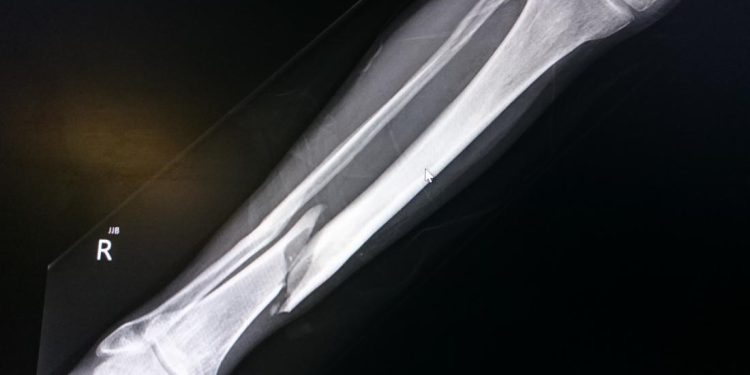

شکستگی استخوان پا ممکن است در اثر ضربه یا نیروی زیاد ایجاد شود. استخوان پا در اثر نیروی زیاد تغییر حالت پیدا کرده یا تکهای از آن ممکن است جدا شود. پا دارای 26 استخوان است که بعضی از این استخوانها بسیار ظریف بوده و در برابر ضربه آسیبپذیر هستند.

- شکستگی مویی: در شکستگی مویی که رایجترین نوع شکستگی استخوان پا است، ترکهایی روی استخوان پا ایجاد میشود که با اشعه ایکس قابل مشاهده خواهند بود. این نوع شکستگی دارای درد کمتری نسبت به دیگر شکستگیها است و درمان آن نیز در بازه زمانی کوتاهتری اتفاق میافتد.